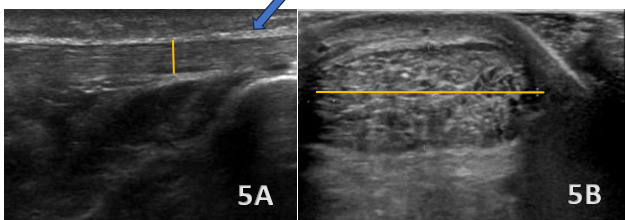

Figures 5A (LAX View) and 5B (SAX View)

In the LAX view, the Achilles tendon is significantly thickened (highlighted with blue arrow in figure 5A), measuring 10 mm in thickness (highlighted in figure 5A with yellow line) and 24 mm in width (highlighted in figure 5B with yellow line), with hypoechoic areas distributed throughout, indicating degenerative changes. This contrasts with the normal mean values for the Achilles tendon, which are typically 4.94 ± 1.24 mm. The SAX view shows an enlarged cross-sectional area with a rounded or irregular contour, heterogeneous echotexture, and hypoechoic regions, further highlighting the tendinopathic changes.